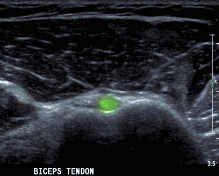

+ Siêu âm đầu dài gân cơ nhị đầu

Tư thế: tay thả lỏng, khuỷu gấp 900, lòng bàn tay ngửa

Kỹ thuật: bắt đầu từ lát cắt qua rãnh gian củ, cắt ngang và dọc theo gân, nghiêng đầu dò lên trên để thăm khám phần gân trong khớp.

Hình 2.29. Hình ảnh siêu âm khảo sát cơ nhị đầu112